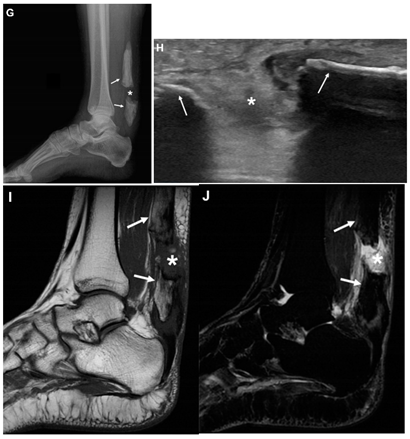

| Romano et al., 2020 d [11] | A 58-year-old woman. This image submission includes a lateral view X-ray (Image G), ultrasound (Image H), MRI (Image I), and STIR image (Image J). In image G the asterisk represents the gap separating the two ossifications (arrows) within the Achilles Tendon. Image H demonstrates a hyperechoic gap (asterisk) between tendon ends (arrows) which is suggestive of a complete rupture of the ossification. Images I and J demonstrate hemorrhage and edema (asterisk) filling the space between the separated ends of the Achilles Tendon. The patient had a palpable gap on examination of the Achilles Tendon. The images confirmed the diagnosis of a complete rupture of ossified tendon. The patient had no history of trauma or surgery in the area. The patient was managed with immobilization in a plaster cast. The patient’s recovery status was not reported. | ![]() |